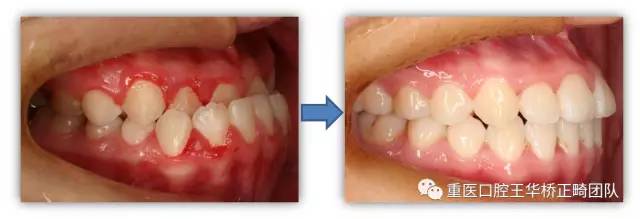

请一起来看一下矫正前后的对比吧

矫正前后牙齿对比